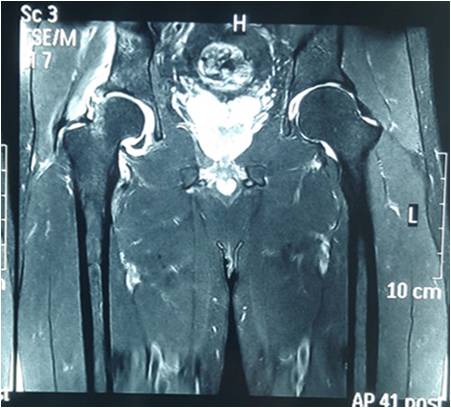

交叉韧带重建